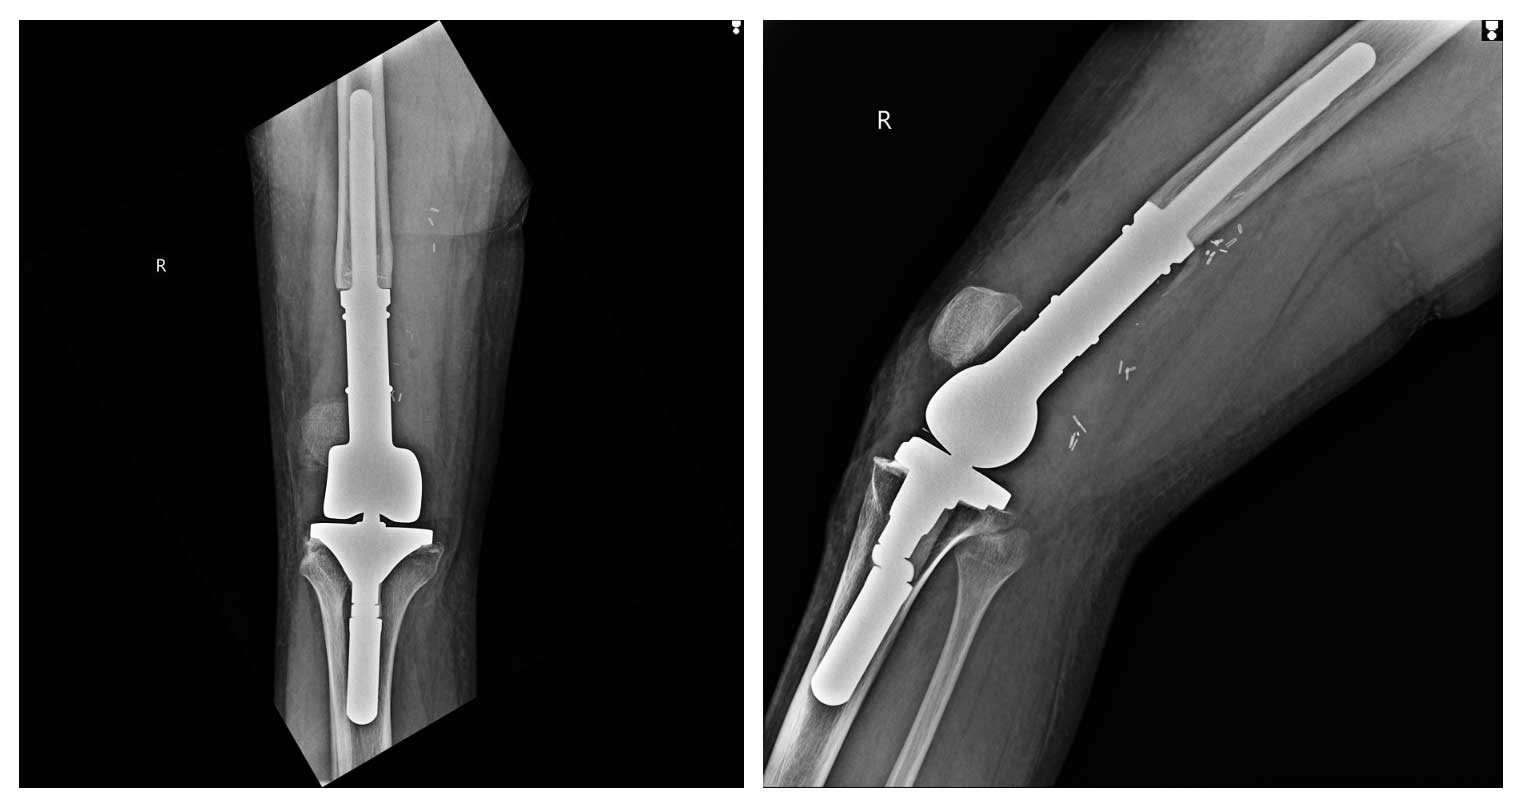

Ameliyat Sonrası: Röntgende tümör çıkarıldıktan sonra uygulanan modüler protez görülmekte.